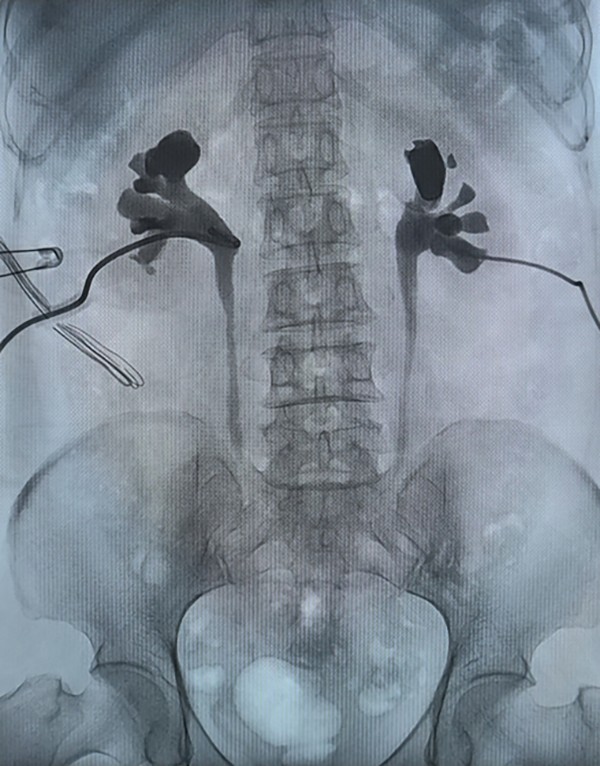

李女士术前损伤造影